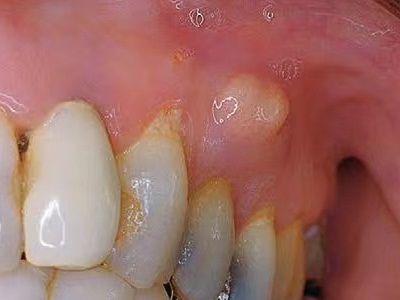

以上为慢性根尖周炎牙龈出现白色小包图。

慢性根尖周炎病程较长,患者的牙龈上可出现根尖脓肿,表现为凸出来的半球形白色小包,邻近的牙齿变色,透出暗黑色,伴有牙齿疼痛感。